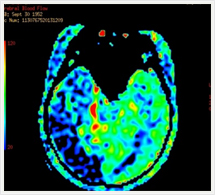

画像紹介

安静時心筋血流シンチグラフィ

心臓の筋肉に酸素や栄養を供給する冠動脈が狭窄または閉塞すると、心臓は虚血状態になり、心筋梗塞に陥ります。心筋細胞の状態(虚血部位、梗塞範囲)を調べる目的で行われる検査です。

6.健康な心臓の筋肉には通常良く集まり、障害がある場合はその障害の程度に応じた集積の低下がみられます。

脳血流シンチグラフィ:脳組織の血流状態を調べる